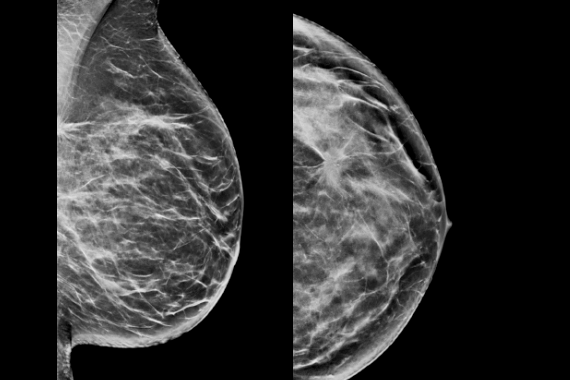

C-View synthesized 2D software

C-View software is Hologic’s FDA-approved solution to replace FFDM within a combined tomosynthesis screening exam. C–View software’s 2D image is designed to be different. Our advanced algorithm takes high quality tomosynthesis data and instantly generates 2D images designed to enhance details such as bright spots and linear structures, while minimizing tissue overlap.

Hologic Low Dose 3D Mammography™ exam powered by C-View software:

Clinically proven to increase invasive cancer detection2-6 and decrease recall rates2,4,5,6,7 compared with 2D alone—just like our original 3D™ mammogram. C-View software progresses early breast cancer detection further by generating a 2D image directly from the tomosynthesis data, lowering patient radiation dose and compression time, with the added benefit of greater patient comfort.